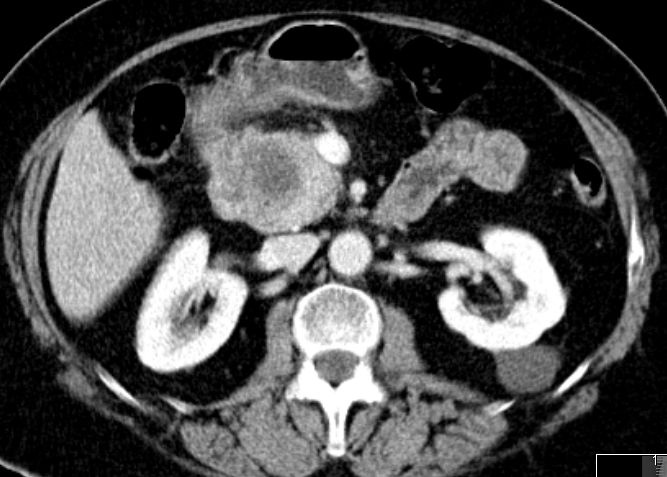

| V. mesenterica superior | 69-jährige Frau mit Pankreaskopfkarzinom. Das CT zeigt eine Infiltration der Vena mesenterica superior.

Nach Laparotomie inoperabel. Infiltrate an der Mesenterialwurzel. Bilidigestive Anastomose, Gastrojejunostomie, Cholezystektomie.![]() | |